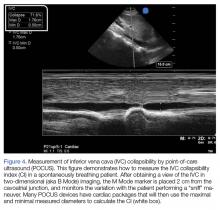

Figure 4.

In the most basic applications, POCUS provides direct visualization of a patient’s cardiac function, presence or absence of lung sliding to suggest a pneumothorax, presence of pulmonary edema, assessment of CVP pressures or potential for fluid responsiveness, as well as identification of potential thoracic, peritoneal, or pelvic cavity fluid accumulation that may suggest hemorrhage. There is literature to support that these assessments performed by the EP have been shown to be comparable to those of cardiologists.59,60 With continued practice and additional training, it is possible for EPs to even perform more “advanced” hemodynamic assessments to both diagnose and guide therapy to patients in shock (Figures 3 and 4).61